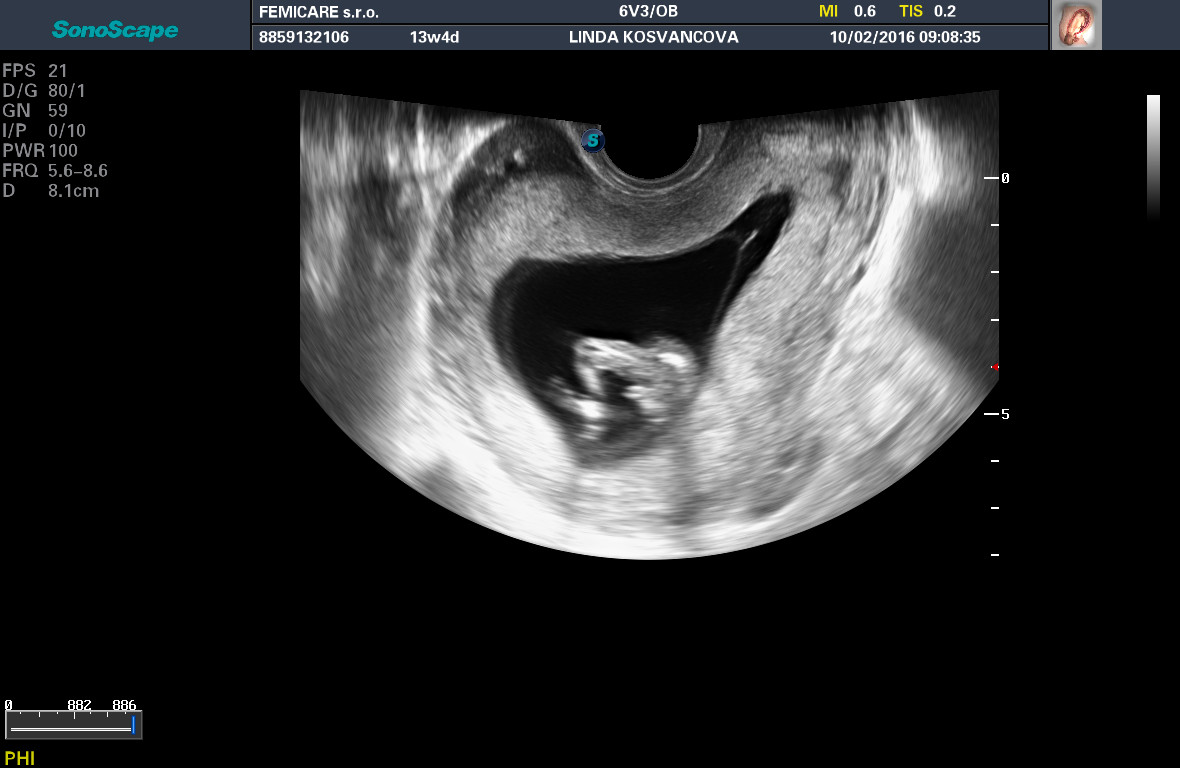

Holky myslíte si, že na téhle fotce z 1.screeningu ve 13tt je něco poznat ? Doktor nám svůj tip řekl, ale ještě se mi na to nechce raději spoléhat, neříkal to zrovna jistě. Děkuji za názory.

avatar

Nám na prvním screeningu řekl že podle pohlavního hrbolku to nepozná ale podle pánve to vypadá na kluka, že to není 100% takže ne že poběžím vykoupit krám :D

Raději si počkej na další vyšetření, aby si třeba nebyla zklamaná, já jdu za týden a už se nemůžu dočkat až se dovím co budeme mít.